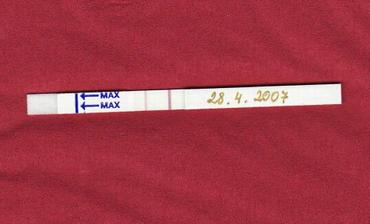

Markétka přišla na svět císařským řezem 21.12.2007 v 5 h ráno v NMB v Brně. Měla 2580g a 48 cm. Maminka byla v 38+1 tt. Těhotenství bylo celkem bezproblémové až na jeho úplný začátek, kdy jsem o něm ještě nevěděla a léčila si zánět po vytržené osmičce, pak až konec, asi 14 dní před porodem přestávala fungovat placenta, bylo málo plodové vody a malá vůbec nepřibírala. Už od narození je Markétka pěkné číslo a dává mamince dost zabrat, ale přesto všechno je to naše sluníčko a už si to bez ní vůbec nedokážeme představit.